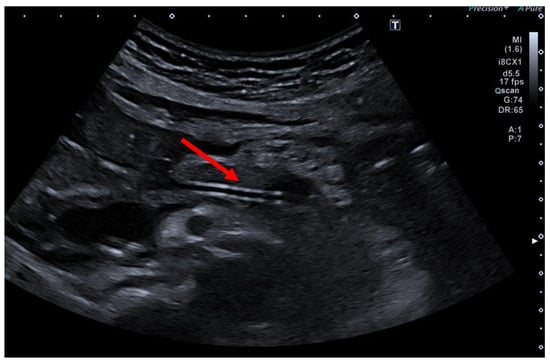

The patient is positioned prone on an X-ray fluoroscopy table and undergoes endoscopic ultrasound (EUS) using a therapeutic longitudinal scanner (e.g., EG 3270 UK, Hitachi Ultraschall, Berlin, Germany; GF-UCT 180, Olympus, Hamburg, Germany; Fuji EG-580UT2, Tokyo, Japan) following unsuccessful conventional ERP, with peri-interventional antibiotic administration i. v. (2 g ceftriaxone or 4 g tazobactam). Once the pancreatic duct is identified, a 19-G needle (Boston Scientific, Ratingen, Germany; Olympus, Hamburg, Germany) is used to puncture it in the direction of the anastomosis or papilla. Pancreatic juice is aspirated and sent for microbiological and cytological examination. Subsequently, the pancreatic duct is visualized via X-ray fluoroscopy following the instillation of the contrast medium (Figure 1 and Figure 2—selected from the clinical picture library of the reporting Dept. of Gastroenterology, Hepatology and General Internal Medicine as all the following figures).

Figure 1. Intraprocedural EUS image: Patients with remitting pancreatitis and dilated pancreatic duct; transgastric EUS-FNA (red arrow) of the dilated duct (blue arrows) and pancreatography (Figure 2), selected from the clinical picture library of the reporting Dept. of Gastroenterology, Hepatology and General Internal Medicine.